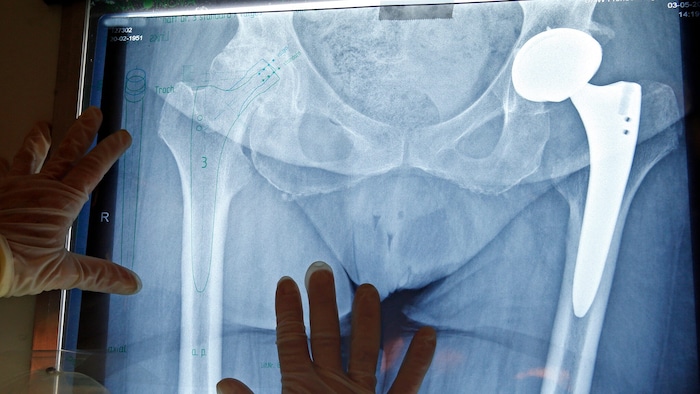

Ein Jahr lang versuchte ein Linzer seine starken Schmerzen an der rechten Hüfte mit Tabletten zu lindern. Als der 63-Jährige schließlich einen Termin in einer orthopädischen Ambulanz hatte, zeigte sich, dass er ein künstliches Hüftgelenk braucht – und er deshalb operiert werden müsse. Der nächste freie Termin wäre in rund eineinhalb Jahren, so die Arbeiterkammer OÖ.

Symbolbild

Symbolbild(Bild: Reinhard Holl)